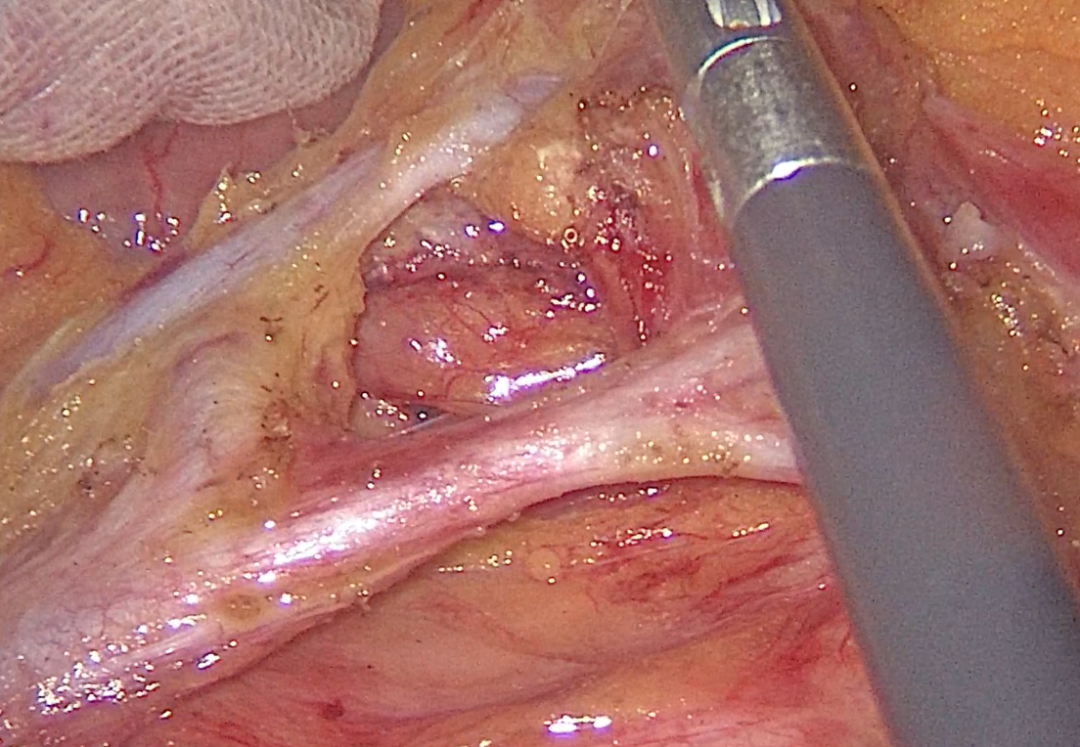

普外科二病区胃肠外科方向专注于胃、结直肠及小肠疾病的规范化诊疗,以“精准微创”为核心技术特色,针对胃癌、结直肠癌,科室常规开展腹腔镜下根治性切除术,术中应用3D、4K腹腔镜高清视野,精准识别血管与淋巴组织,实现肿瘤完整切除的同时,最大限度保护正常组织。

右半结肠癌术后术野展示

胃癌术后术野展示及标本展示

直肠癌根治术后术野展示和标本展示